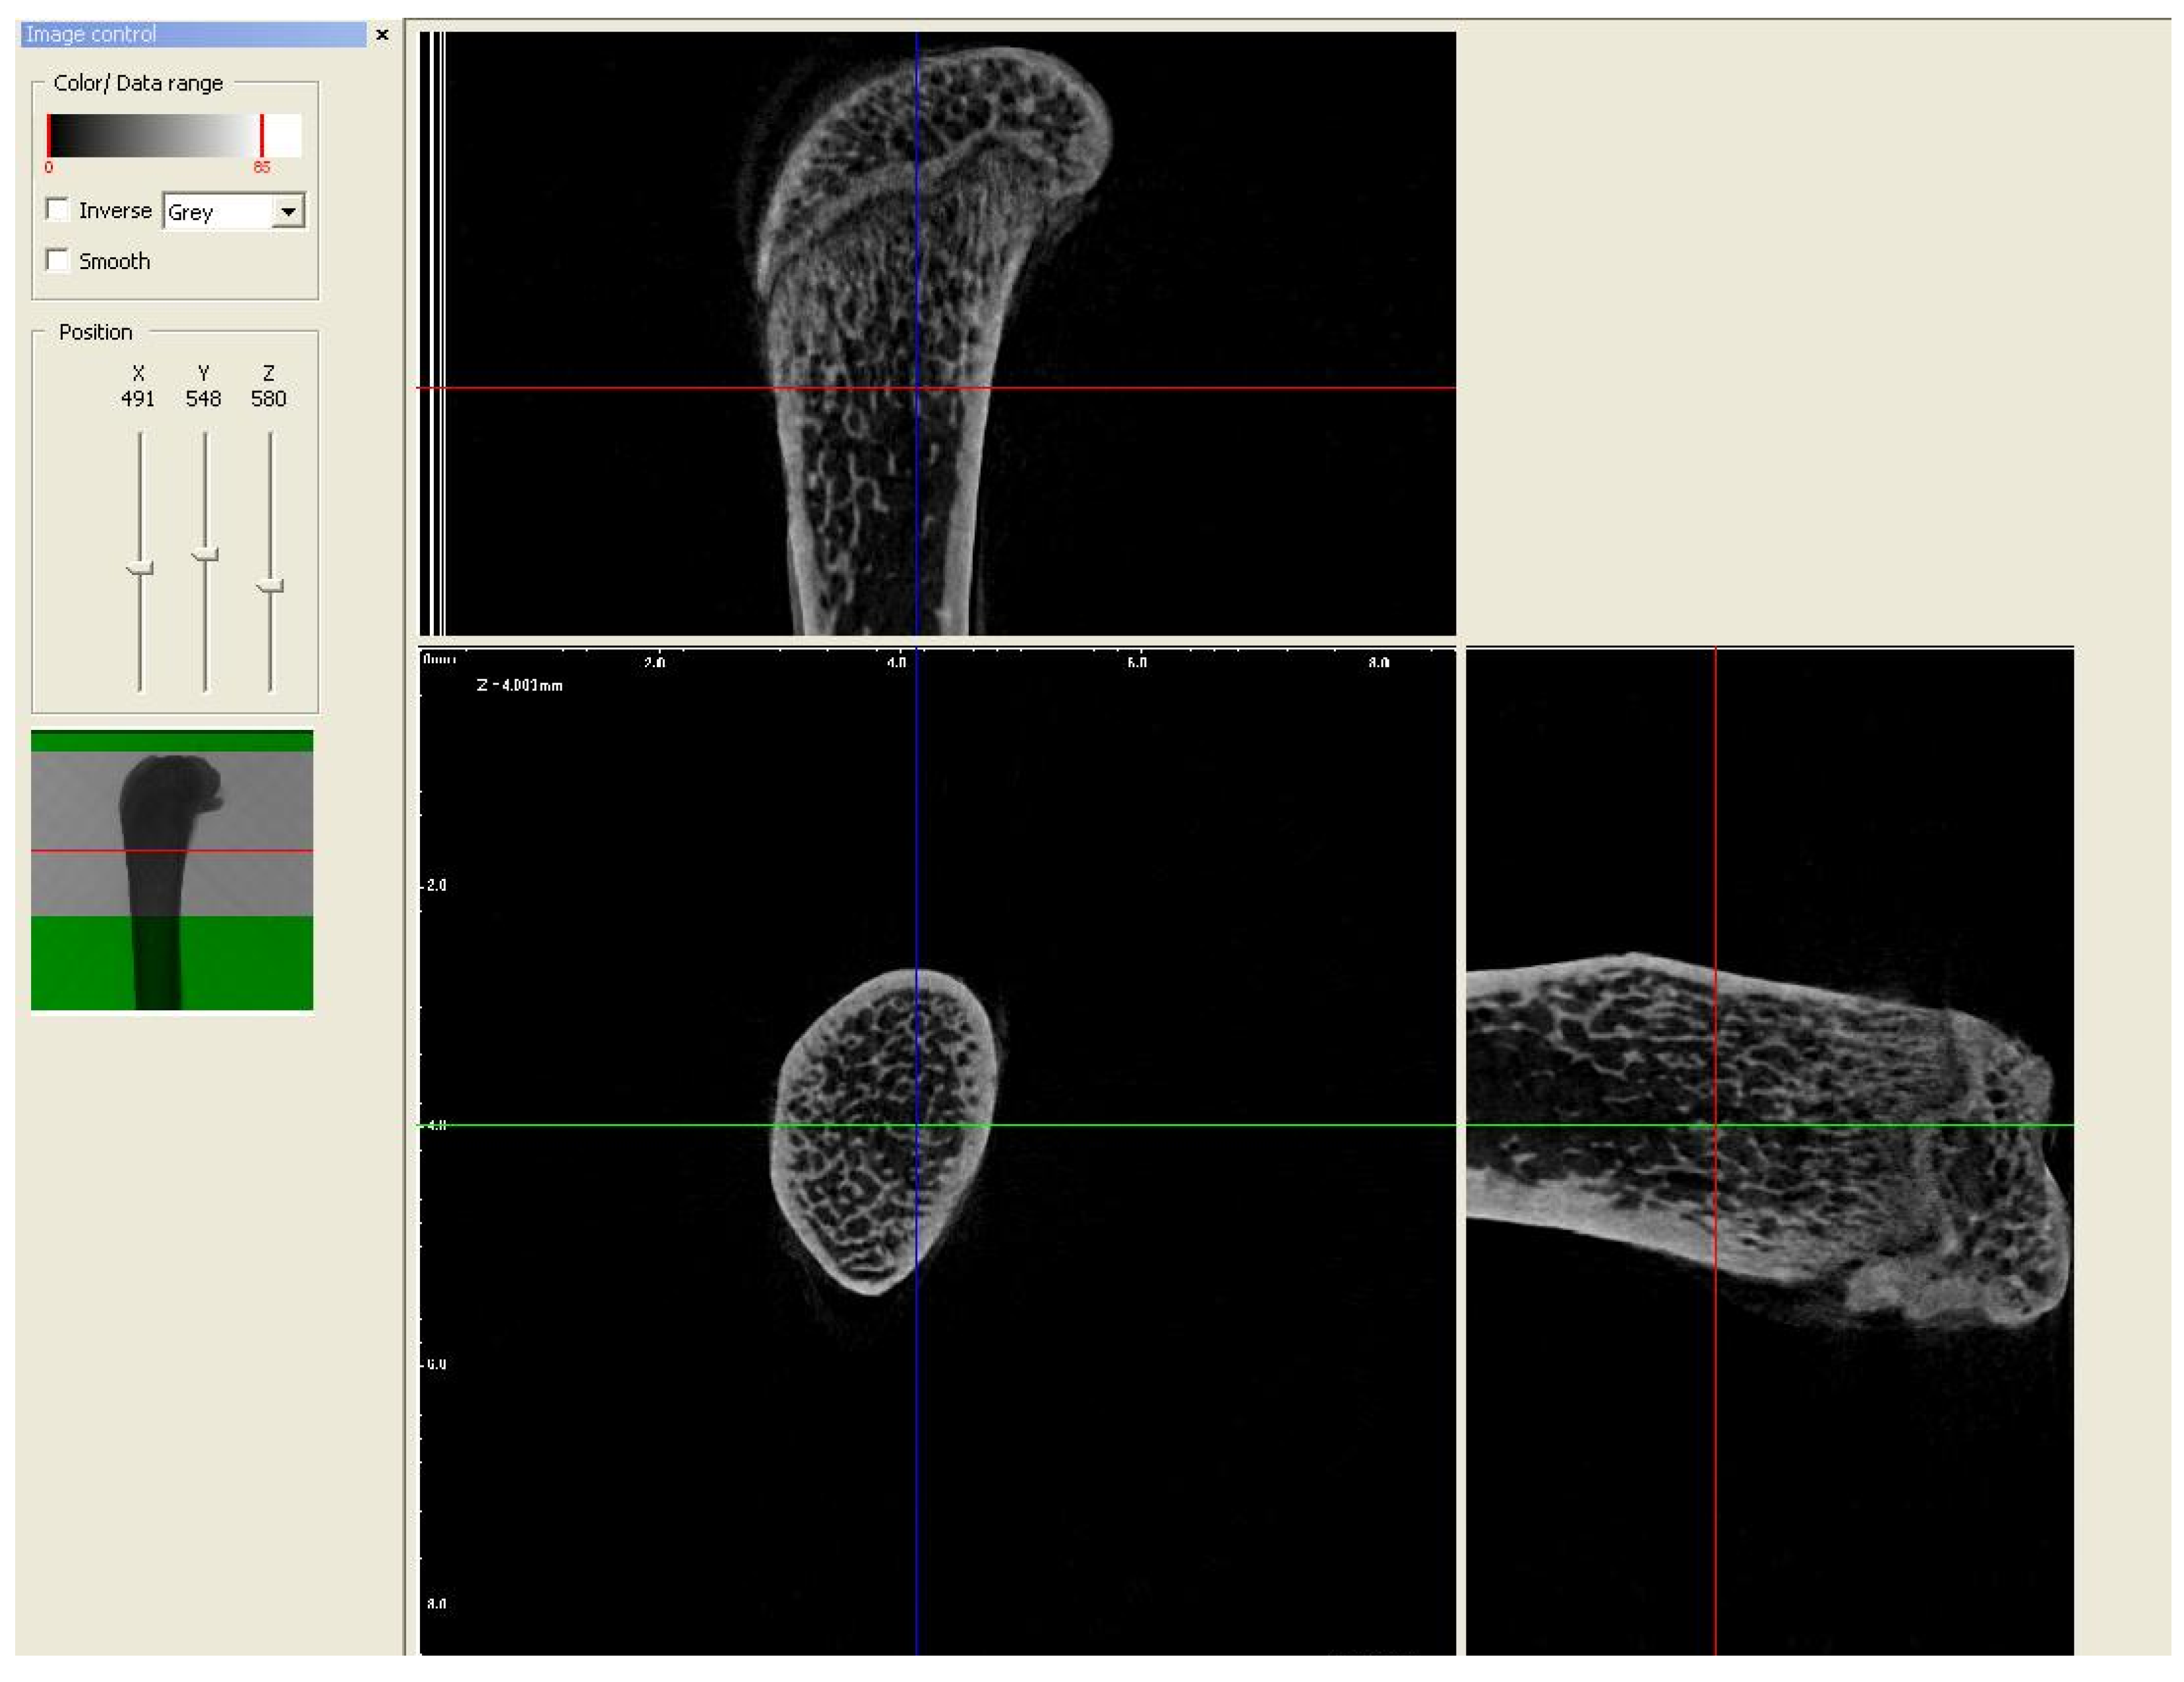

2.2. Micro-CT Analysis

3.3.1. Trabecular Thickness (Tb.Th), Trabecular Number (Tb.N), and Percent of Bone Volume (BV/TV)

3.3.2. Trabecular Separation

3.4. Cortical Bone Area